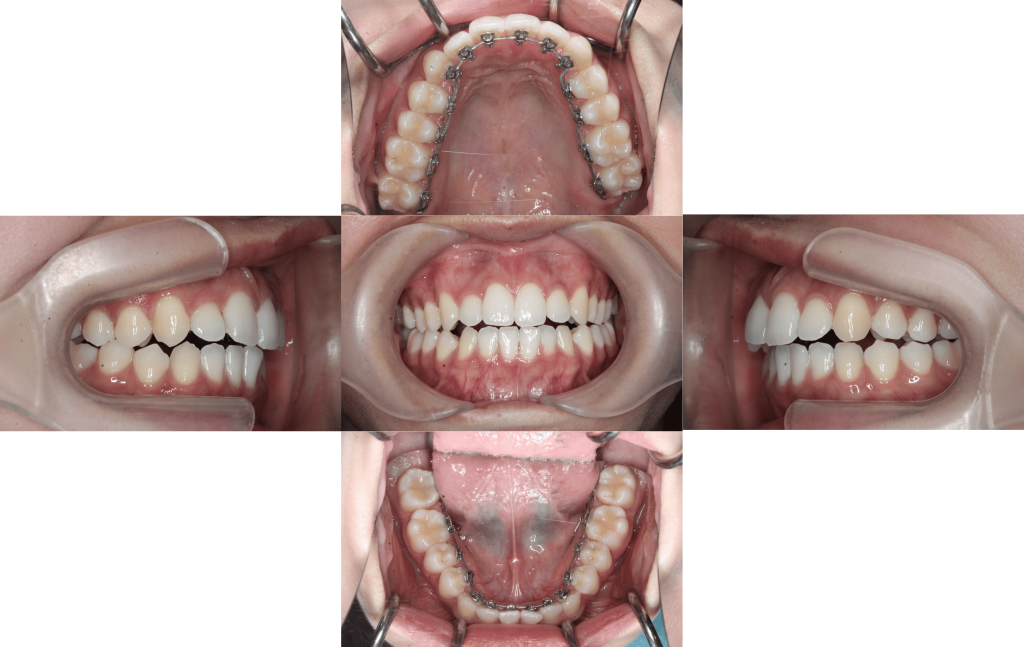

装置装着